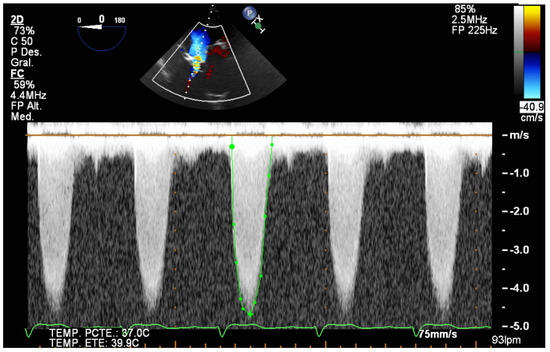

- Confirm the proper position of the guide and the balloon through the aortic valve (Videos S5 and S8);

- Confirm cessation of valve movement during high-frequency pacing;

- Confirm the correct position of the prosthesis prior to inflation. However, it is not always easy to identify the ends of the prosthesis when it is still retracted on the balloon. The 3D mode will help in the correct identification of its ends (Video S10). If the prosthesis is too low, it can affect the mitral valve, and if it is too high, it can migrate distally or cause coronary obstruction. It should be taken into account that during inflation the prosthesis usually moves about 3 mm in the aortic direction.